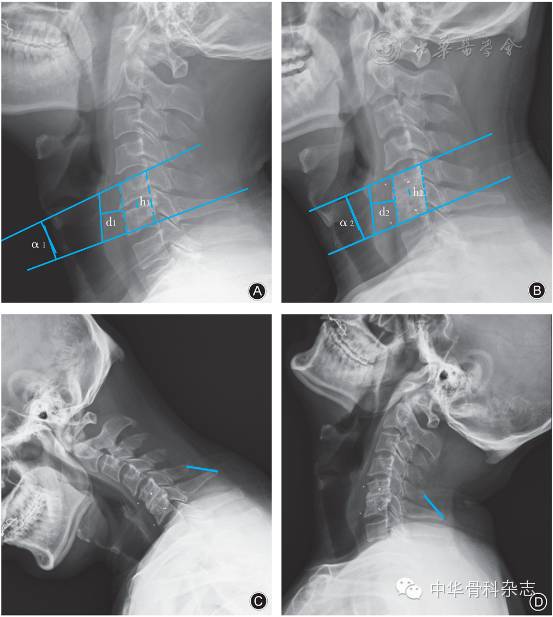

图3 男,53岁,右上肢疼痛伴行走不稳4年,诊断为脊髓型颈椎病,行前路颈椎间盘切除融合术A术前侧位X线片示C5,6节段椎间隙狭窄,局部反弓,测量C5,6节段Cobb角(α1=-5.38°),椎间隙高度(h1=37.9 mm),椎前软组织厚度(d1=16.9 mm)B术后13个月侧位X线片示C5,6节段椎间隙骨性融合,测量C5,6节段Cobb角(α2=0.38°),椎间隙高度(h2=37.8 mm),椎前软组织厚度(d2=16.4 mm)C, D术后13个月过屈、过伸位X线片,测量C5及C6椎体棘突间距离(标线)在过屈位及过伸位相等